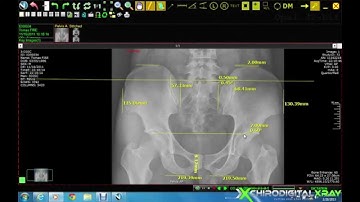

Digital X-ray Software Demo